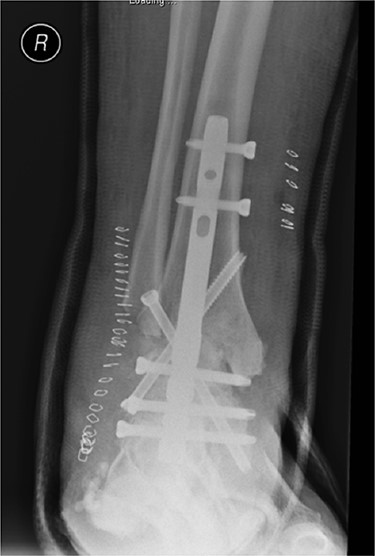

In May 2015, he had a complex midfoot reconstruction, but his foot continued to drift into varus. This was complicated by an infected ulcer on the lateral aspect of midfoot (Fig. 3). Wound infection progressed to osteomyelitis, and in May 2018, he had a hindfoot reconstruction with fusion of tibiotalar and subtalar joints using a Cerament-V-coated hindfoot nail (Figs 4 and 5).

Anterior–posterior radiograph of right ankle demonstrating tibiotalocalcaneal fusion using a hindfoot nail and screws.

Preoperatively, radiographs were used to template and to determine the size of the nail. The canal was over reamed by 4 mm: 2 mm of which accommodated for the Cerament mantle, with a further 2 mm to minimise friction during nail insertion. Reamings were sent to microbiology. The canal was washed thoroughly with saline pulsed lavage, gloves were changed and the patient re-draped.

A BIOMET hindfoot nail was attached to its jig and prepared using a single preparation of 10-ml Cerament-V. When in its fluid phase, the Cerament-V was passed through a syringe to cover the nail. The nail was rotated during the setting process such to attain a uniform and smooth surface (Figs 6 and 7). A 14 mm gauge was used to ensure a 2 mm (× 2) thickness of Cerament was achieved. The nail was subsequently inspected such to exclude any defects in the mantle. There was adequate time to ensure that the Cerament had set. Interlocking screw holes were not sited as this may have damaged the cement mould.

The nail was inserted under guidance from fluoroscopy. Proximal and distal locking was performed through the standard jigs (Fig. 8).